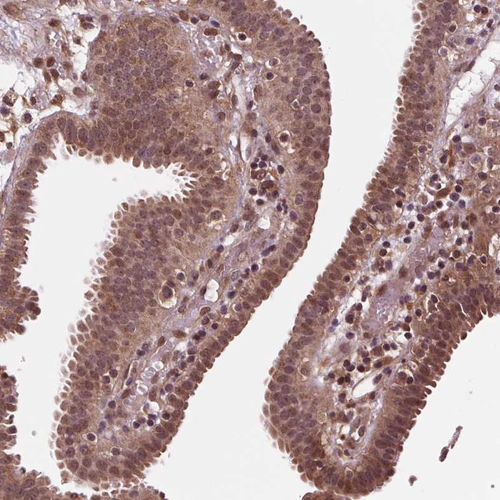

Immunohistochemical staining of human spleen shows moderate cytoplasmic positivity in cells in red pulp.